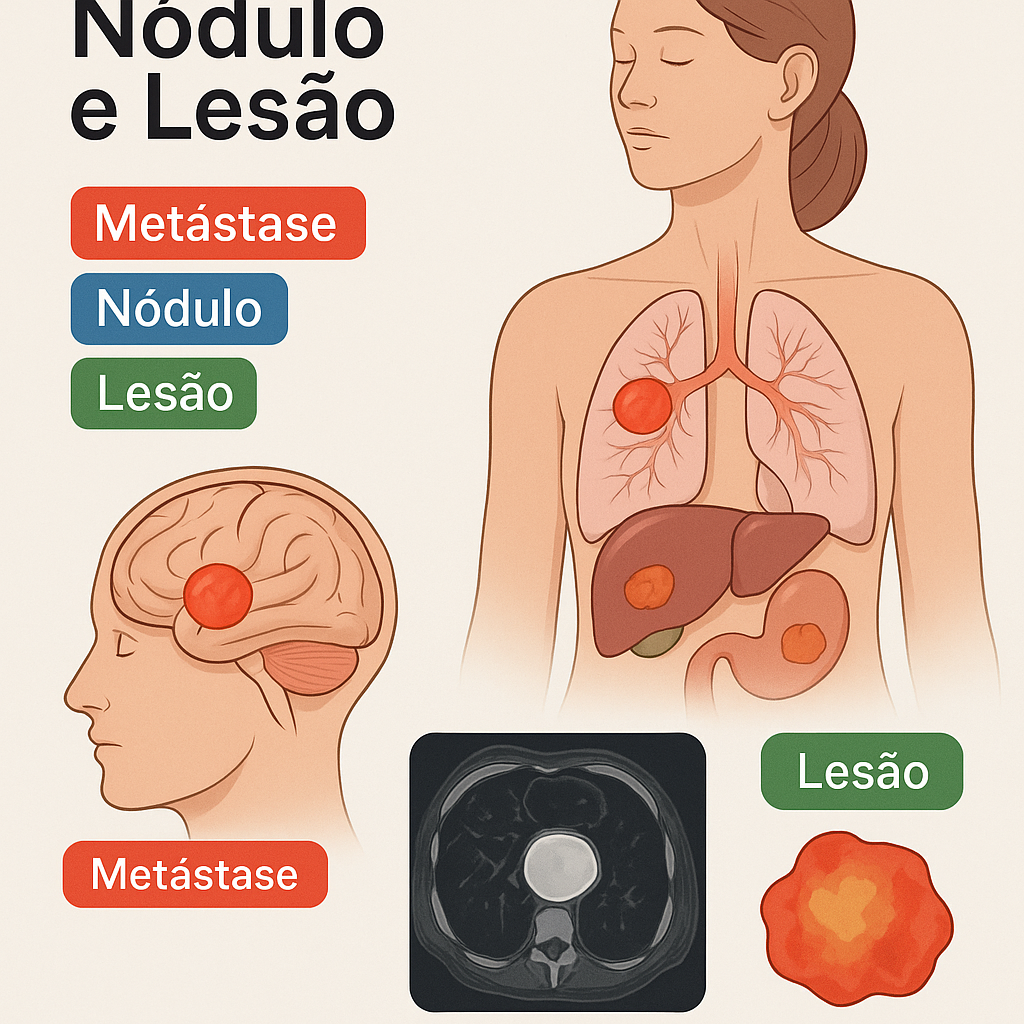

Aprenda as diferenças clínicas e radiológicas entre metástase, nódulo e lesão, com exemplos práticos e tabelas.

Saiba mais